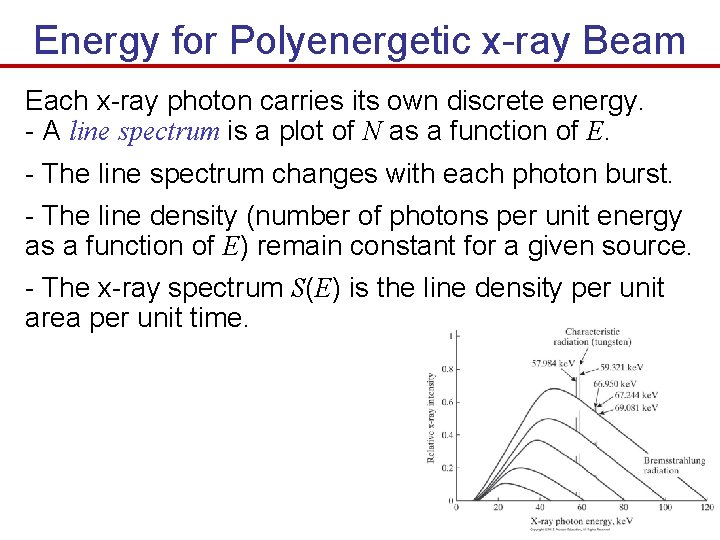

Energy for Polyenergetic x-ray Beam Each x-ray photon carries its own discrete energy. - A line spectrum is a plot of N as a function of E. - The line spectrum changes with each photon burst. - The line density (number of photons per unit energy as a function of E) remain constant for a given source. - The x-ray spectrum S(E) is the line density per unit area per unit time.